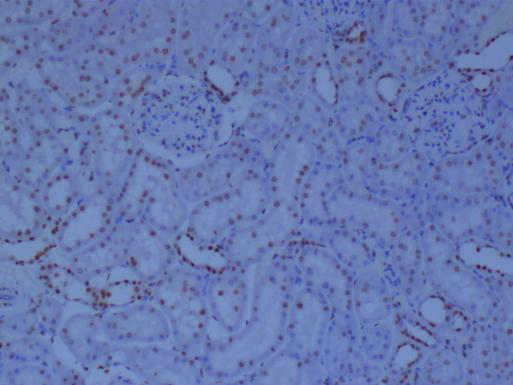

冰凍切片還可以用于免疫組化研究。通過冰凍切片技術(shù),研究人員可以制備含有特定抗原的組織切片,進而利用免疫組化方法檢測和分析抗原的表達情況。這對于研究細胞的生物學(xué)功能、疾病的發(fā)生機制以及藥物的療效評價具有重要意義。

由于冰凍切片能夠較好地保存組織的化學(xué)成分,因此也適用于組織化學(xué)分析。例如,研究人員可以利用冰凍切片技術(shù)制備含有特定酶類或代謝產(chǎn)物的組織切片,進而進行酶活性測定、代謝產(chǎn)物檢測等分析。這有助于揭示組織的代謝途徑、功能狀態(tài)以及與疾病的關(guān)系。